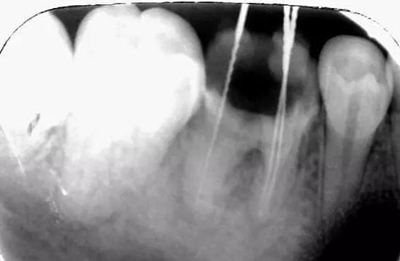

初診時X光片:根分歧炎癥懷疑有底穿,和患者交待病情和費用后開始治療。

初尖銼,根測儀測量長度后拍照

初尖銼X光片:現(xiàn)在根測儀的準(zhǔn)確性的卻非常之高。